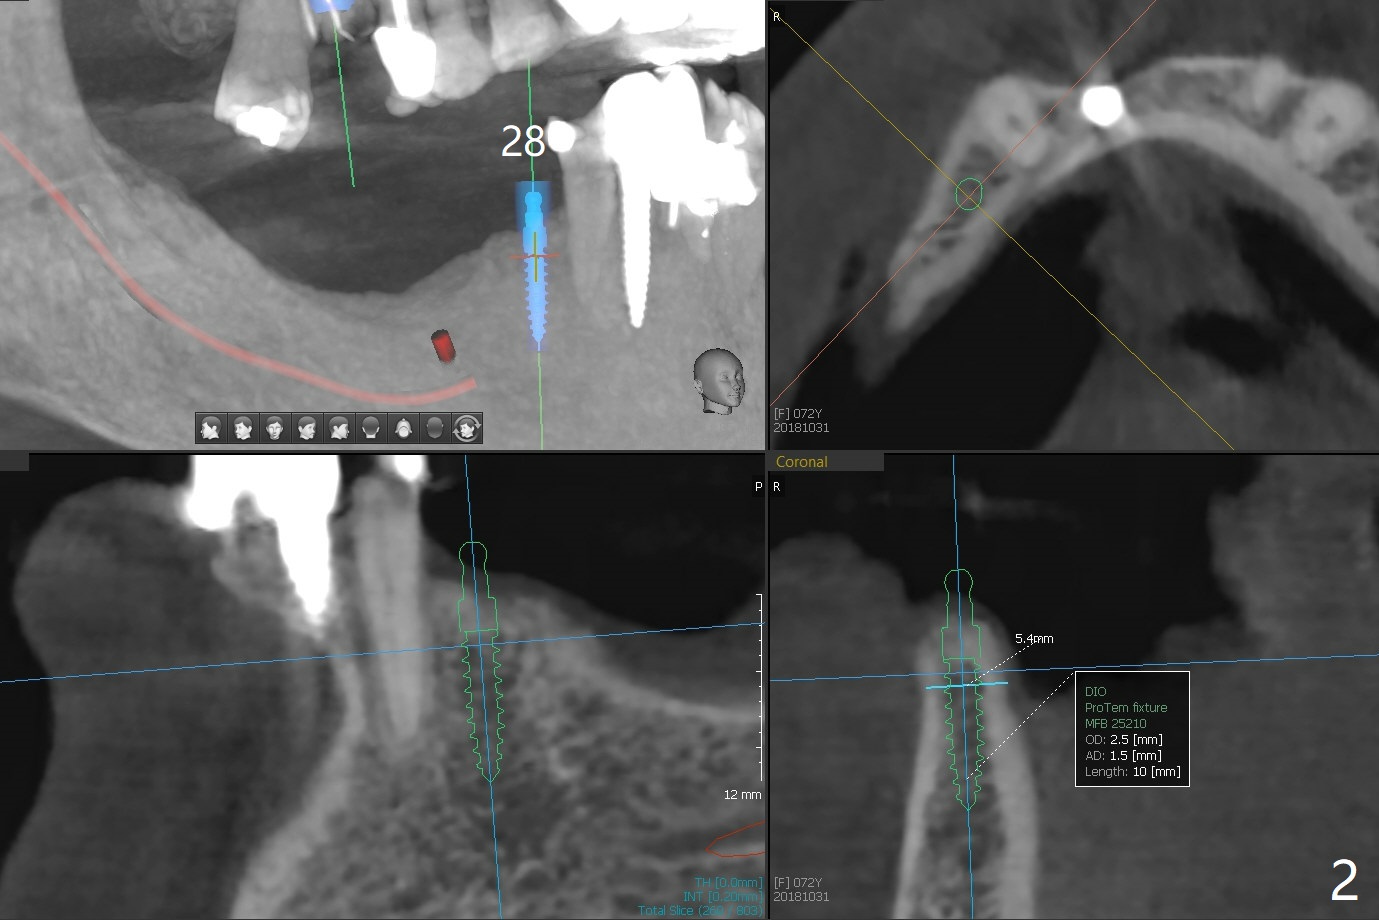

74岁女要求重做下颌局部托牙(图一(三年前(3号牙种植之前)拍摄)),因为lingual bar压迫牙龈,多次调整无效。准备在28和31牙位种植,做覆盖托牙(overdenture)。由于28牙位牙槽嵴窄,31牙位骨质短,准备使用导板植入2.5毫米一段式植体(图二,三),后者带有球状基台。